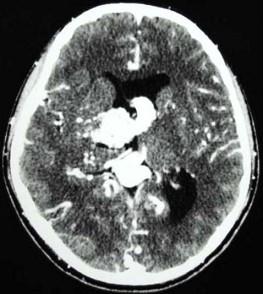

问题 男,32岁,头痛、癫痫,查体发现视乳头水肿,CT检查如图,最可能的诊断为()

选项 A.结节状硬化 B.钙化灶 C.动静脉畸形 D.少突胶质瘤 E.脑囊虫

答案 C